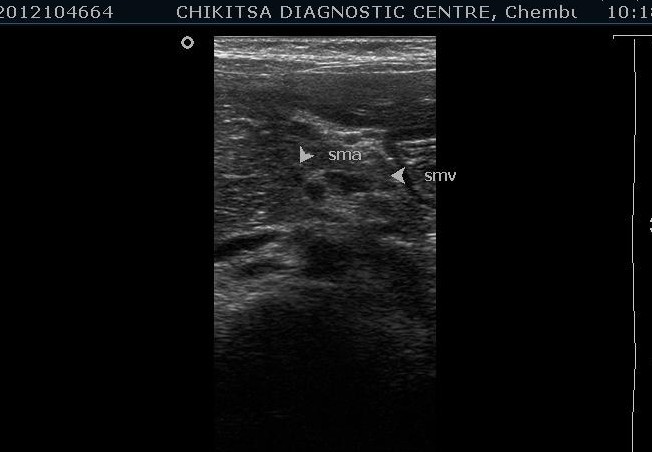

Should exclude hypertrophic pyloric stenosis and then the relationship between the SMA and SMV should be assessed. In normal population, the SMV is to the right of SMA. The SMA is smaller, round and surrounded by fat, however the SMV is larger and has a thinner wall. In malrotation/volvuls the SMV is to the left of the SMA.

Whirlpool sign consists of a side-by-side arrangement of vessels with opposing flow directions, indicating that the whirlpool contains not only the SMV and its tributaries but also branches of the SMA.